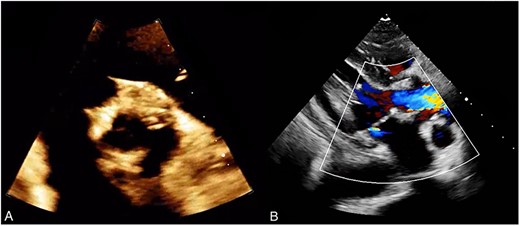

A thorough cardiovascular examination was performed, which revealed normal prosthetic valve clicks and a grade 3 ejection systolic murmur in the right second parasternal space. Further investigations included a transesophageal echocardiogram (TEE), which showed a paravalular anechoic free space around the prosthetic mechanical aortic valve with paravalular leakage and regurgitant flow with dehiscence of the prosthesis causing aortic stenosis (Fig. 1). A computed tomography (CT) scan was also performed to rule out aortic calcification, which revealed a normally seated aortic valve prosthesis with no visualization of the paravalular free space (Fig. 2). During the preoperative workup, blood cultures showed bacterial growth of Brucella melitensis. A multidisciplinary team approach was initiated, and the patient was started on antimicrobial therapy with gentamicin, doxycycline and rifampin. However, due to the patient developing abnormally high levels of Aspartate aminotransferase (AST) and Alanine aminotransferase (ALT), which is a side effect of rifampin, the regimen was changed to ceftriaxone, doxycycline and trimethoprim/sulfamethoxazole.

Preoperative TEE: (A) Red arrow pointing at a paravalvular anechoic free space around the prosthetic mechanical aortic valve. (B) Echo image showing paravalvular regurgitation and leakage around the prosthetic mechanical valve. (C) 3D reconstructive echocardiography image showing paravalvular free space around the aortic mechanical valve at 3–9 o’clock with aneurysmal echo free space at the aortomitral curtain protruding into left atrium. (D) Aortic prosthetic mechanical valve dehiscence causing aortic stenosis with moderate paravalvular regurgitation.